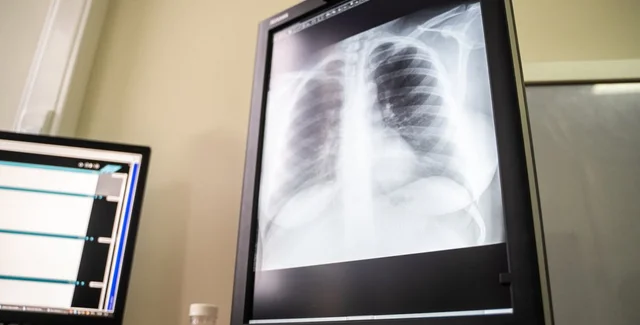

Коронавирус, ослабляя иммунитет, может спровоцировать переход бессимптомного туберкулеза в активную фазу

После перенесенного коронавируса у людей с бессимптомным протеканием туберкулеза последний может перейти в активную форму, передает РБК со ссылкой на данных министерства здравоохранения РФ.

"После перенесенного COVID-19 у многих пациентов в легких формируются выраженные остаточные изменения в виде фиброза. Можно предположить, что эта категория пациентов имеет повышенный риск развития туберкулеза в последующем", – говорится в рекомендациях ведомства по профилактике и лечению коронавируса.

Опираясь на данные Всемирной организации здравоохранения, в министерстве отметили, что туберкулез в скрытой форме протекает у трети больных по всему миру. Из-за коронавируса в крови пациента снижается число циркулирующих лейкоцитов и общее число лимфоцитов, из-за чего организм становится более уязвимым для сопутствующих заболеваний и активизации туберкулеза, если таковой есть.